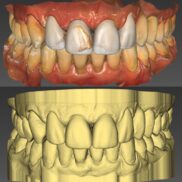

Konsultoinnin aikana selvisi, että etuhampaissa on runsaasti huonoja täytteitä. Yhteistyössä asiakkaan kanssa päätimme, että kauniin ”hymyrivin” aikaansaamiseksi tulisi yläleuan etuhampaisiin laittaa 10 kruunua tai laminaattia ja alaleuassa korjata kuluneet tai rikkoontuneet poskihampaat keraamisilla kruunuilla. Lopputuloksen visualisoimiseen ja asiakkaalle esittelemiseen valmistimme vahamallin.

Yhteistyössä asiakkaan kanssa päätimme, että hampaiden asennon oikaisemiseksi ja esteettisen ulkonäön saavuttamiseksi on kuusi hammasta peitettävä laminaateilla ja yhteen hampaaseen laitetaan kruunu. Lopputuloksen visualisoimiseen ja asiakkaalle esittelemiseen valmistimme vahamallin.